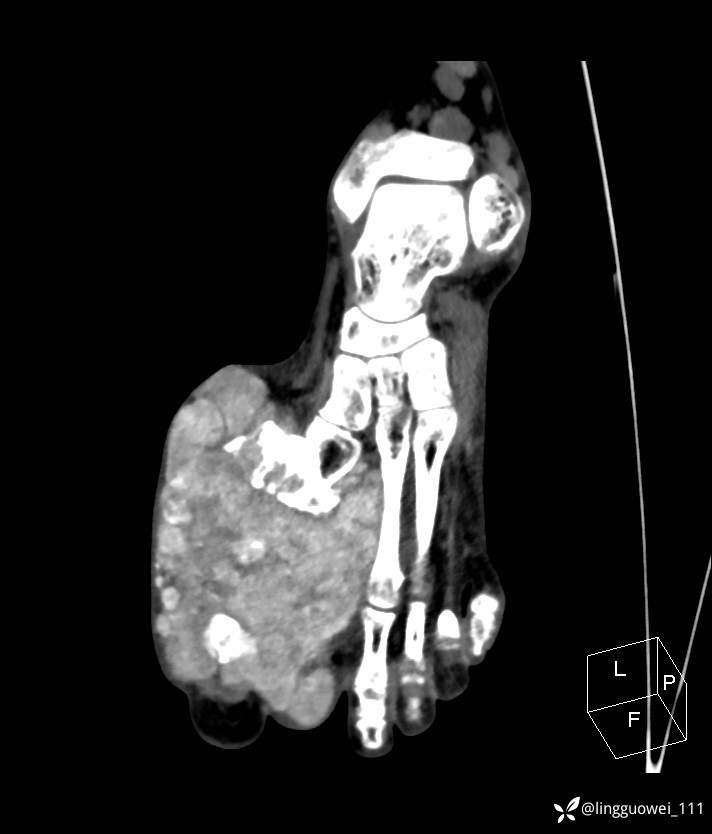

28岁男性,工作中遇到的足部最大的肿块,已补充临床资料。

28岁男性,足部肿块逐渐增大2年。能找到病因吗?

患者于2年余前高嘌呤饮食及大量饮酒后出现全身多处关节痛风石,以右足第一跖趾关节和右手为显,局部红肿热痛反复发作,自行口服药物后可缓解(药物可疑为强的松、双氯芬酸钠等,具体不详)。2年来右足痛风石明显增大,约10cm*5cm*15cm,局部红肿发热,3天前患者再次大量饮酒后痛风石顶部破溃,可见4cm*3cm皮损,较多白色豆渣样分泌物流出,为求进一步治疗来诊,门诊诊断为“右足痛风石破溃伴感染”, 收住院拟手术治疗,患者起病以来,无发热,精神佳、胃纳好、睡眠佳,大小便正常。

专科检查:右足外观畸形,足背部可见巨大痛风石形成,痛风石大小约10cm*5cm*15cm,局部皮肤红肿发热,痛风石顶部破溃,可见4cm*3cm皮损及白色豆渣样分泌物流出;痛风石界限清,质偏硬,局部触及波动感,无压痛,移动度差。右足踇趾及第2趾被痛风石压迫,关节活动受限。肢端血运、感觉无异常。 右手稍肿胀,2-5指背侧可见多发痛风石形成,最大者约花生米大小,皮肤完整未破溃,痛风石界限清,质偏硬,局部触及波动感,无压痛,移动度差。

检验:尿酸672,白细胞1.5万